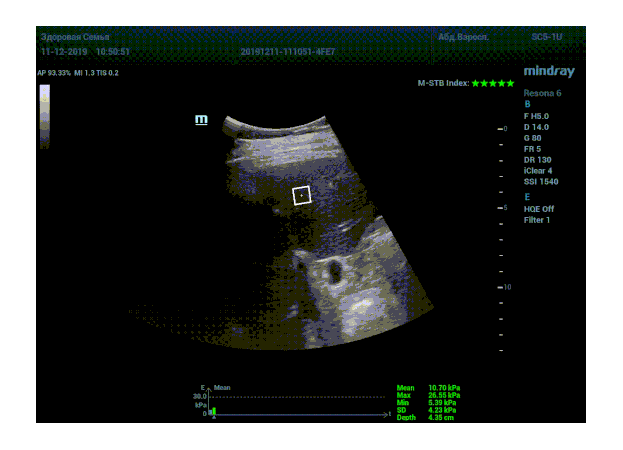

Определение плотности печени. Не ошибся ли оператор при измерении эластических свойств печени? Для оценки критериев качества предусмотрен индекс MBT, который покажет насколько «твердой» была рука оператора и двигалась ли печень. При MBT 5* рука тверда и показатели достоверны. Для оценки качества результатов используется IQR индекс, отображающий колебания показателей в точке измерения при расчете медианы. Показатели при IQR <30% считаются приемлемыми. Техника сканирования через межреберные промежутки требует размещение окна интереса на несколько сантиметром ниже капсулы, для исключения эффекта реверберации. Установка ROI на паренхиму без захвата сосудов, для исключения погрешностей измерения.

Стадия фиброза определяется по системе METAVIR Staging, построенной на данных биопсии и сопоставлении с данными эластографии. Своевременная диагностика фиброза, и начало его лечения, залог благоприятного исхода заболевания.

• METAVIRF0 – норма.

• METAVIRF1 – Портальный фиброз без вовлечения перегородок

• METAVIRF2 – Портальный фиброз с вовлечением нескольких перегородок

• METAVIRF3 – Портальный фиброз с вовлечением множества перегородок

• METAVIRF4 – Цирроз.